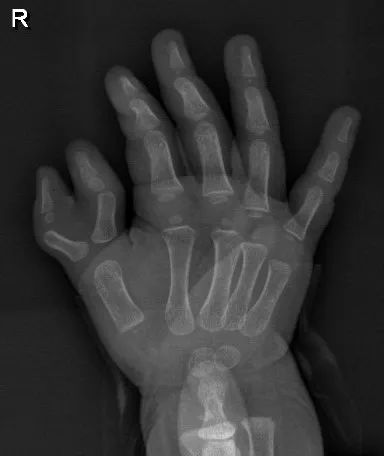

小明患有先天性右手拇指多指,兩個 “拇指”共用一個掌指關(guān)節(jié),每個都比正常的拇指要小,且指間關(guān)節(jié)畸形,看上去像“老虎鉗”,又像蟹鉗。

手術(shù)中,醫(yī)生先切除外側(cè)手指的指骨,保留皮膚軟組織,保留掌指關(guān)節(jié)囊組織,重新修復(fù)掌指關(guān)節(jié)囊,矯正內(nèi)側(cè)拇指向內(nèi)側(cè)偏斜畸形,然后將保留下來的近節(jié)指骨進(jìn)行部分截斷并(如下圖)“掰直”,從而重塑外觀,恢復(fù)功能。

張金明教授介紹,“蟹鉗樣”多指是多指中較難處理的一類,屬于Wassel分型中的4型匯聚型。兩個指頭對向側(cè)彎,形同螃蟹的兩個鉗子,故稱“蟹鉗樣”多指。